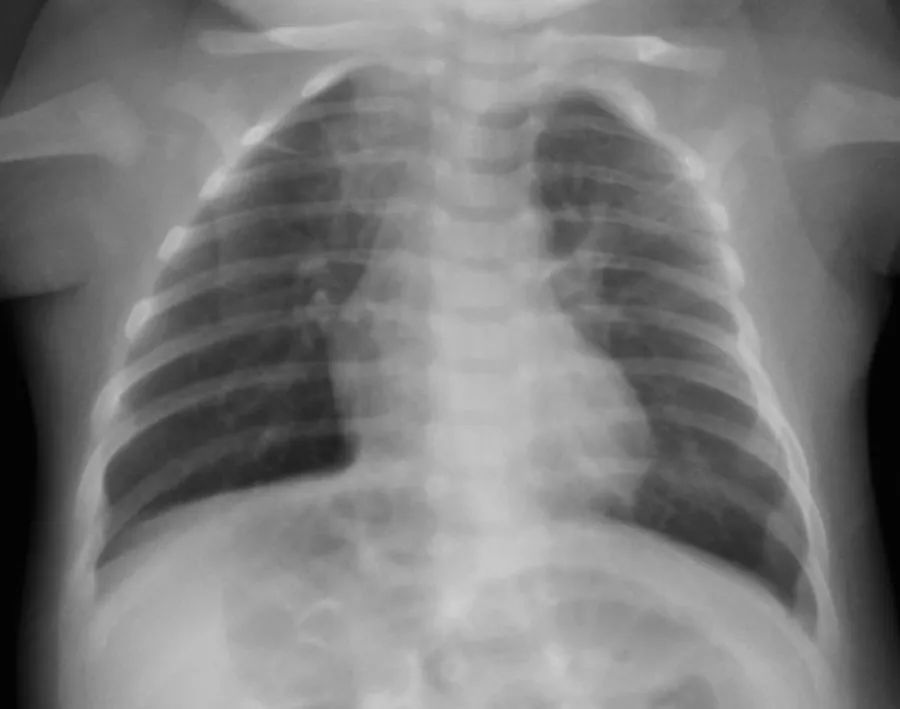

2月龄时,曾因咳嗽、发热做过X线胸片。后经过对症治疗,痊愈。

X线胸片,腋下钙化灶。